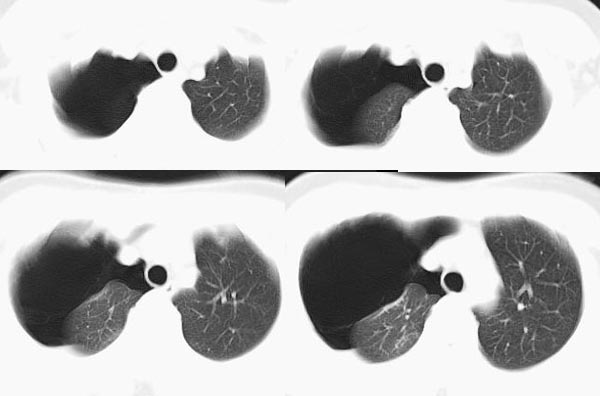

m21y既往体健,否认结核、支扩等病史;1周前患上感,无明显咳嗽,自觉无明显不适。单位体检透视时发现右侧液气胸!cr及ct如下(肺组织窗:l:-598hu w:1132hu):请大家会诊!!

右侧巨大含气囊性病变,壁薄、光整、其外侧见气体。右肺压迫性肺不张、胸腔内见少量积液。纵隔向左侧移位。左肺未见异常。诊断:1.右侧含气肺囊肿(先天性)。2.右侧液气胸。(少量液体)3.右肺压迫性肺不张。我也遇见一例这样的病人。女性。股骨外伤就诊。常规胸片发现右侧囊性病变。